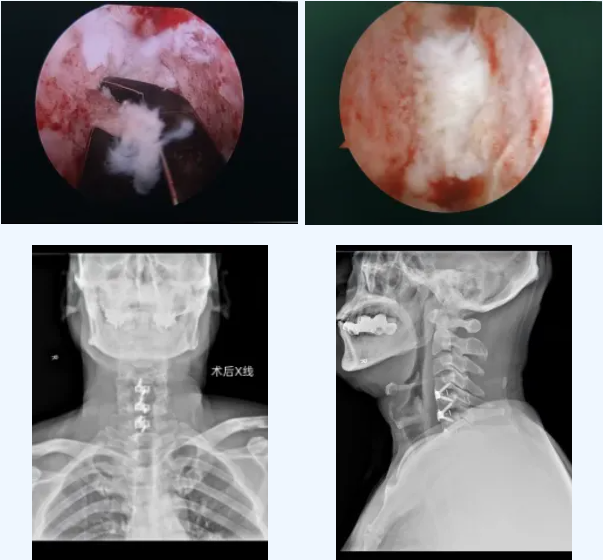

面对徐先生明确的脊髓压迫和神经损伤,必须尽快手术减压。李永革主任团队经周密评估,为患者量身定制了方案:采用 UBE(单侧双通道内镜)技术施行颈前路微创减压融合术。

这项技术的核心优势在于 “精准”与“微创”:

视野放大20倍:4K高清内镜让压迫部位一目了然,实现“可视化”精准操作;

减压更彻底、更安全:可在镜下轻柔、彻底地切除脱出的椎间盘,解除脊髓压迫,极大避免损伤周边神经血管;

保留结构:无需大范围切除椎体,保留了颈椎原有稳定结构;

康复更快:配合使用低剖面内固定,减少术后吞咽不适,特别有利于中老年患者快速恢复。

手术由李主任主刀,顺利清除了致压物,脊髓压迫彻底解除,颈椎稳定性也得到重建。整个过程出血少、创伤小。